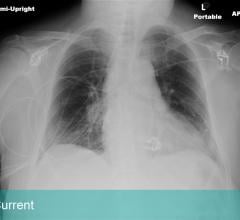

“Lung cancer is the deadliest cancer in men and in women, and it all boils down to how it is detected and when it is ...